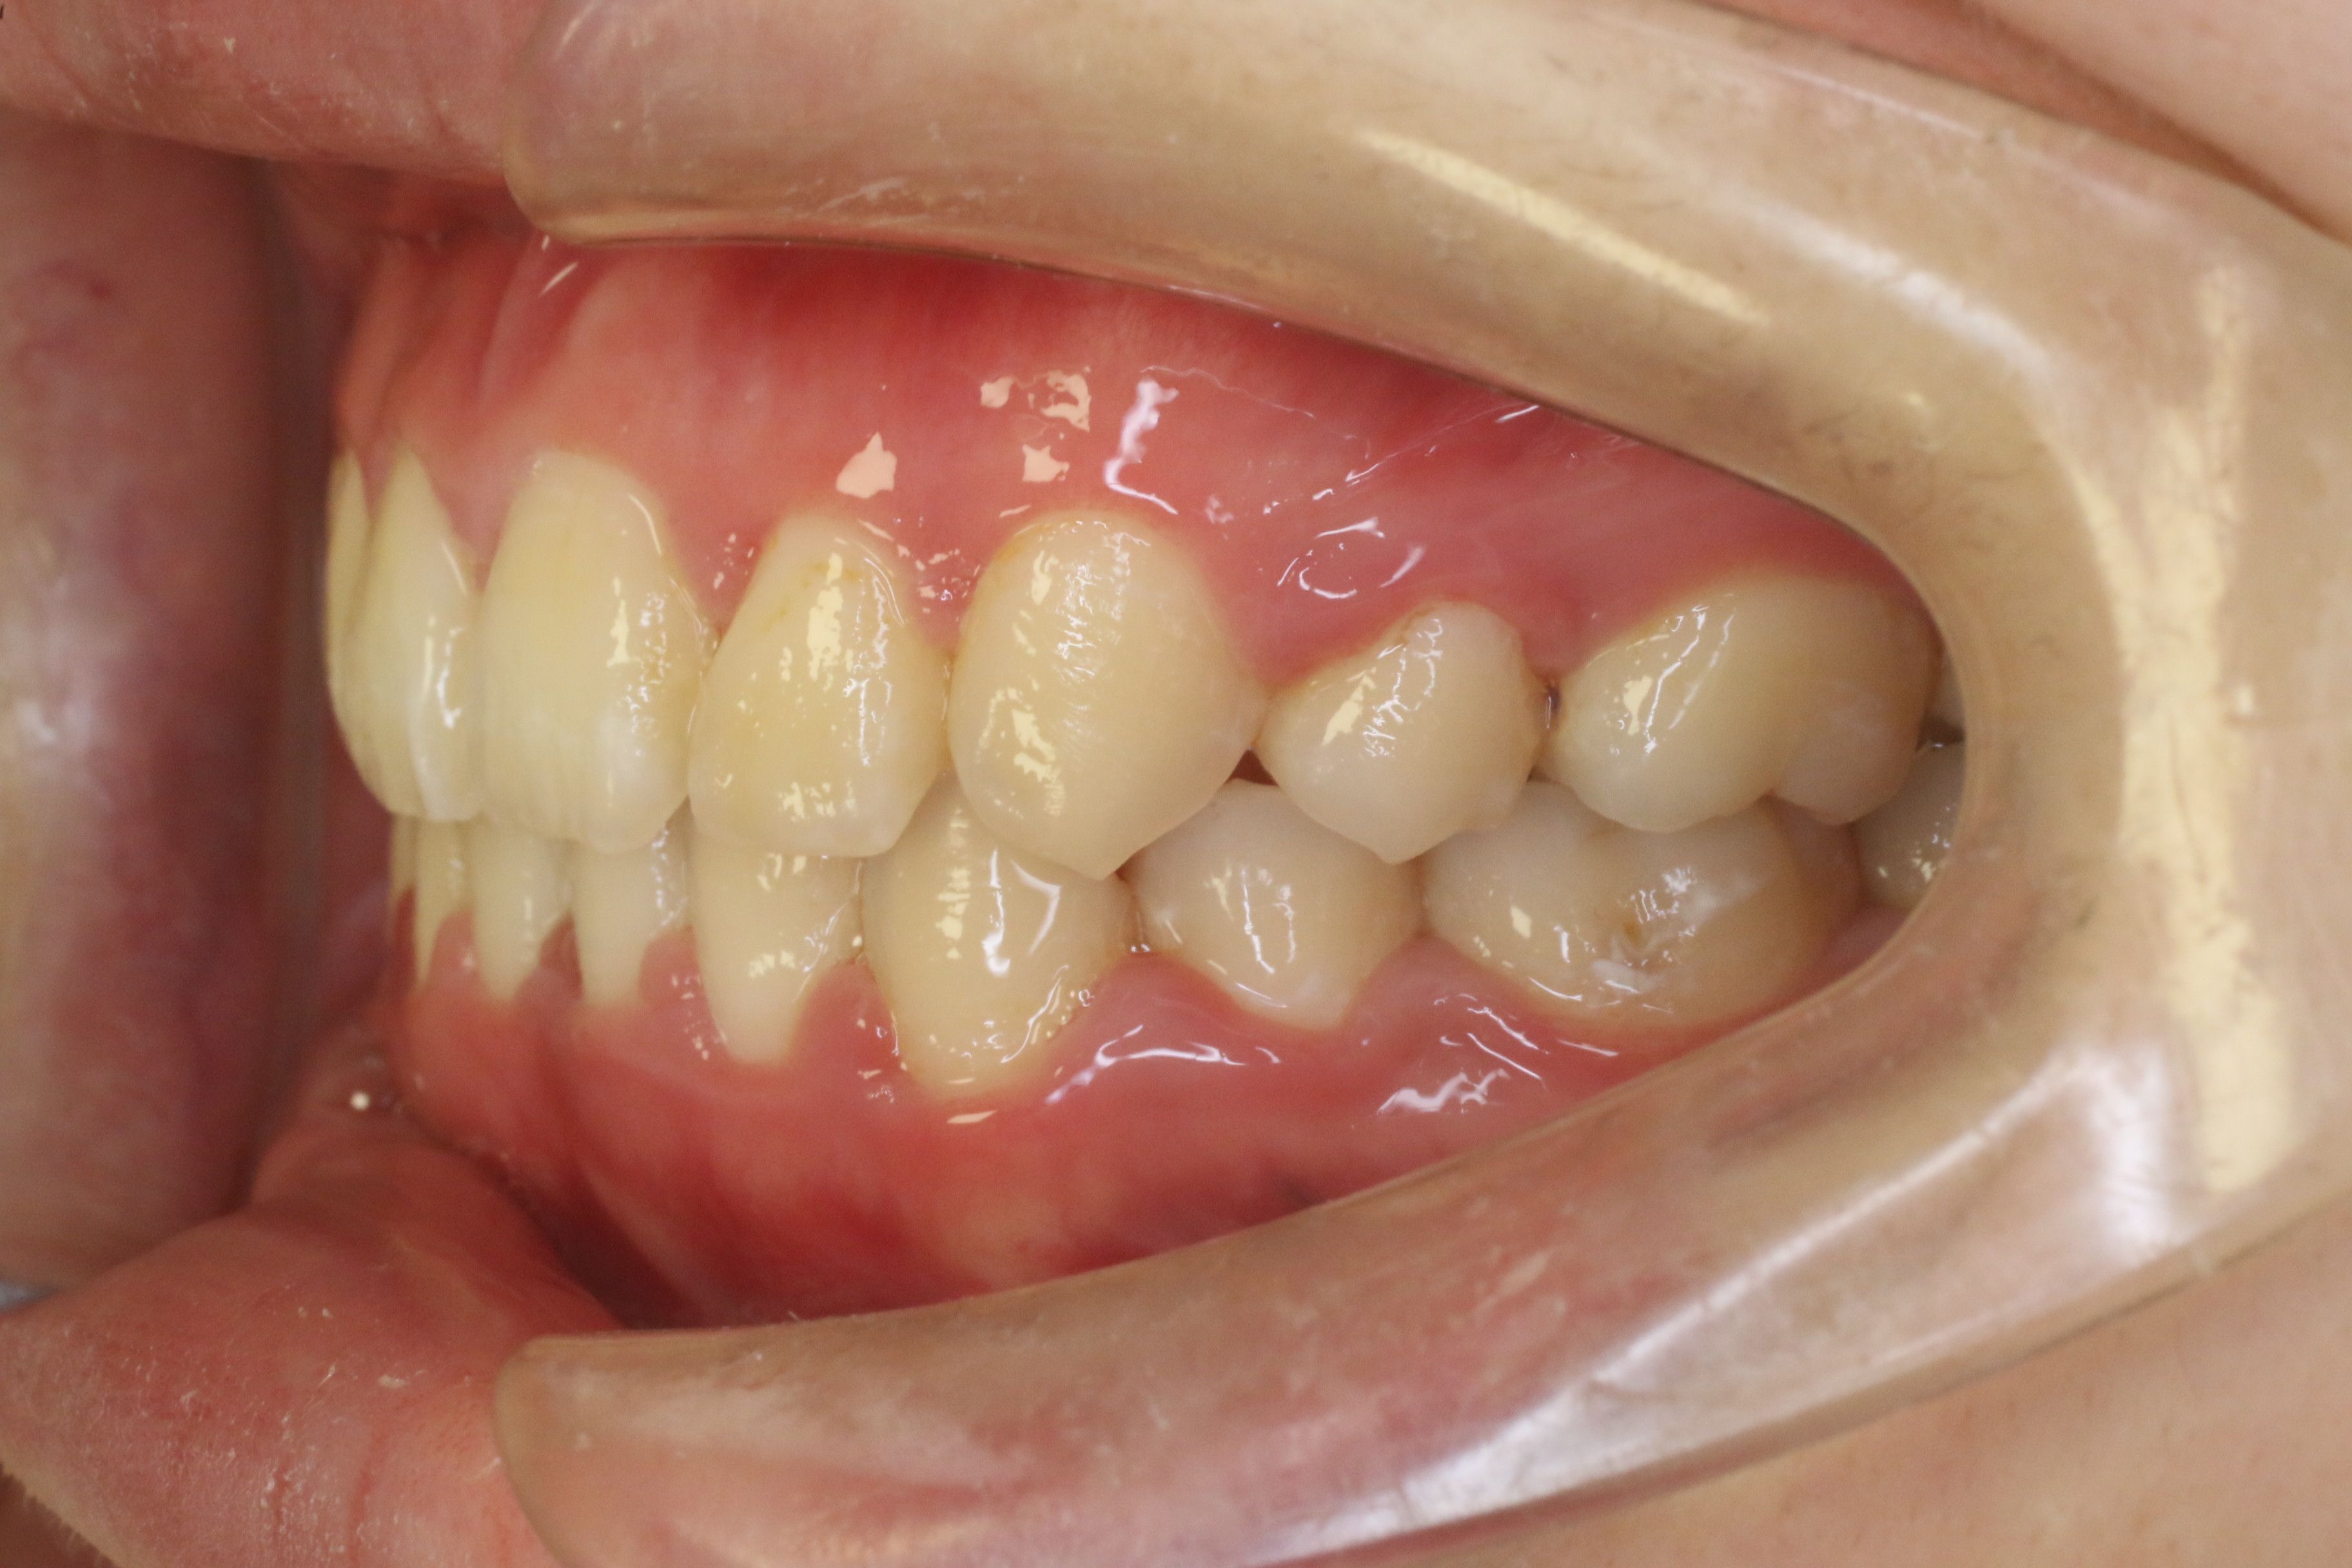

受け口を治したい

年齢層 20代

性別 女性

主訴 【主訴】受け口を治したい 【診断・症状】反対咬合、上下凸凹

治療費用 検査・診断:38,500-/ハーフリンガル矯正治療:1,287,000-(※全て税込)

治療期間 約1年半(20回)

抜歯 無(非抜歯)

矯正の装置 ハーフリンガル矯正

副作用、リスク 歯肉退縮,歯根吸収,疼痛,咬合の違和感,装置の違和感,虫歯,歯肉炎

case17_受け口_before

Before

case17_受け口_after

After